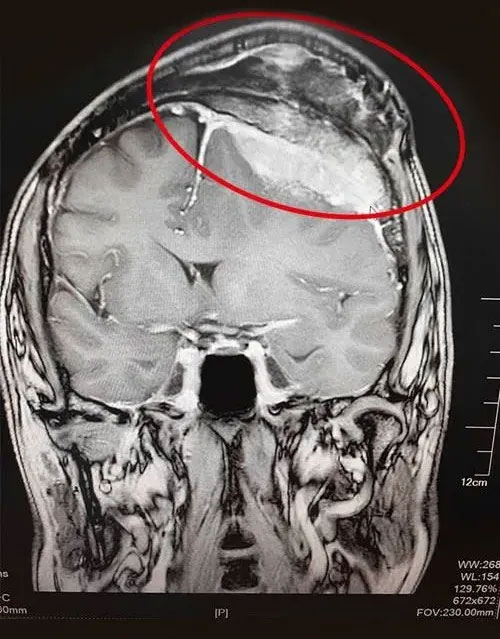

▲ 巨大脑膜瘤图例